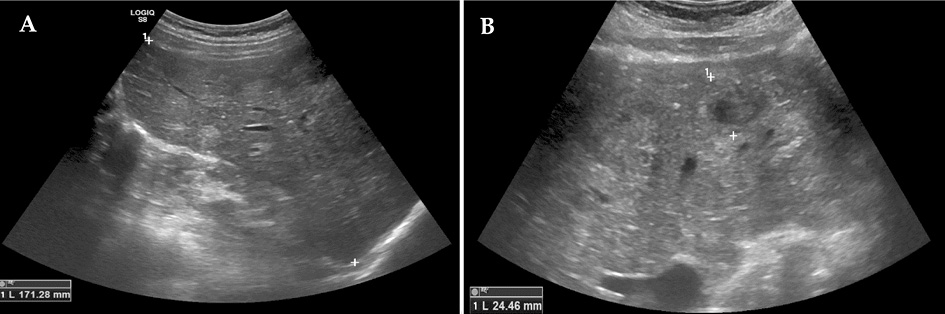

The abdominal ultrasound revealed hepatomegaly (right lobe ~171 mm) and multiple variable echogenicity liver metastases (part of which was degrading) throughout all liver segments (the biggest ~25 mm in diameter) (Figure 1, A, B). A nonhomogenous increased uterus with several calcified myomas was also observed.

Figure 1. Abdominal ultrasound images. Hepatomegaly and multiple variable echogenicity liver lesions (metastases) throughout all liver segments (the biggest ~25 mm in diameter) (A, B).